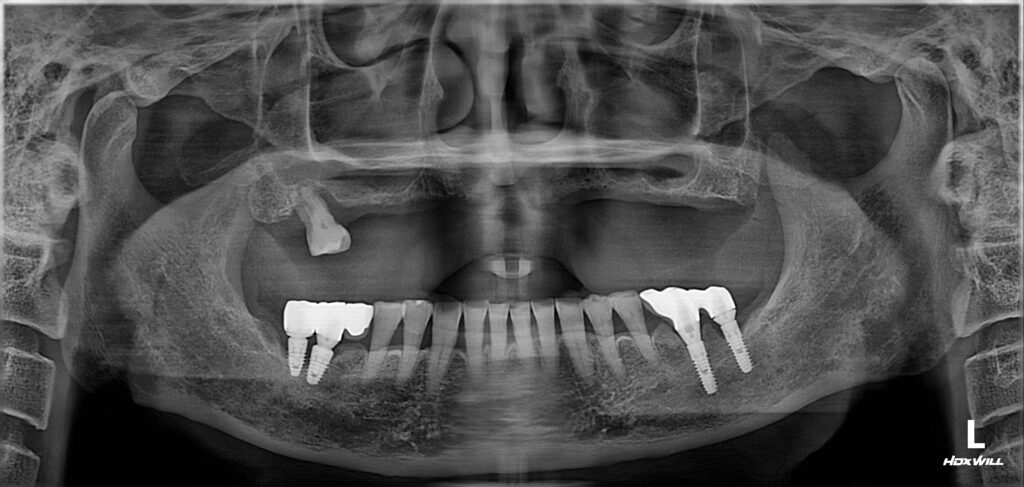

이번에 내원하신 환자분은 60대 남성분으로, 아래 치아는 모두 존재하지만 위쪽 치아는 하나도 없는 상태였습니다.

전체 임플란트 수술 완료

양쪽 상악동 거상술을 포함해서 수술을 완료했습니다.

보셔서 아시겠지만 아주 좋은 위치와 간격으로 임플란트가 식립된 것을 볼 수가 있습니다.

이렇게 원칙을 잘 지켜서 섬세하게 식립한 임플란트는 추후에 오랫동안 튼튼하게 제 기능을 할 가능성이 매우 높습니다.